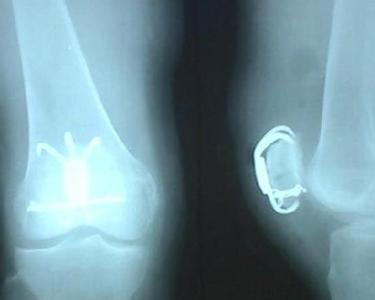

髌骨骨折是较常见的损伤,以髌骨局部肿胀、疼痛、膝关节不能自主伸直,常有皮下淤斑以及膝部皮肤擦伤为主要表现的骨折。髌骨骨折的发生年龄一般在20~50岁之间,男性多于女性,约为2:1。